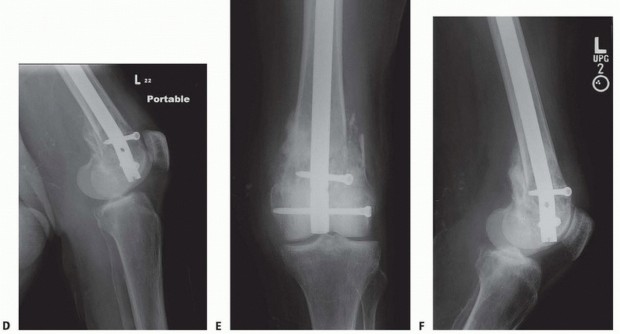

### FIG 9 • Critically ill elderly polytrauma Jehovah's witness patient with left C1 distal femur fracture. A,B. Initial injury AP and lateral views. C,D. Due to extremely low hematocrit, external fixation was the only surgical option allowed to minimize blood loss. Radiographs in bridging external fixation. The AP shows excellent alignment but the lateral shows the expected extension deformity secondary to pull of gastrocsoleus complex. E,F. After 5 weeks in an external fixator, AP and lateral radiographs show callus formation (red arrows). Patient is now cleared for definitive surgical intervention. Antegrade intramedullary nailing has been described and can be used for distal fractures with a large enough distal segment to allow for two locking screws. Malalignment has been a problem, as has adequate fixation. 4, 8 Retrograde intramedullary nailing can be used in the following cases ( FIG 10): All extra-articular type A fractures greater than 4 cm from the joint. This minimal length of the distal femur allows for multiplanar interlocking in the distal fragment. Type C1 or C2 fractures where the articular fracture can be anatomically reduced closed or with limited exposure. Percutaneous screws are used for the articular injury. Periprosthetic fractures around a total knee arthroplasty with an “open box” femoral component Most surgeons prefer to use a long nail, but short supracondylar nails are available as well. Multiple-hole short supracondylar nails have fallen out of favor. Plate fixation ORIF with plates can be used for all types A and C fractures but is ideal for the following injuries: Very distal type A fractures within 4 cm of the knee joint All articular type C fractures, but always for C3 types Periprosthetic fractures about a “closed box” femoral component of a total knee arthroplasty The partial articular type B1 or B2 if an antiglide plate is needed Plate options (preferred to least preferred; fixed-angle devices preferred) Fixed-angle locking plates (percutaneous jigs are advantageous and allow for minimally invasive techniques) Variable-angle (polyaxial) locking plates—allow for “fixed variable locking” within a defined range. It is useful for distal fractures and allows for increased screw 473 trajectories to gain additional locked fixation in short segments, which may not be feasible with fixed-angle trajectory plates ( FIG 11).

---

### FIG 10 • A,B. AP and lateral radiographs of an elderly patient with multiple comorbidities with an extra-articular distal femur fracture (AO type A; an incomplete intercondylar split— red dashed arrow). C,D. Postoperative radiographs showing stabilization with retrograde intramedullary nail. E,F. One-year postoperative radiographs showing a healed fracture with some subsidence of the metaphyseal region and mild protrusion of hardware through the notch. Ninety-five-degree condylar screw Ninety-five-degree blade plate Nonlocking plates with or without medial support (medial plate or external fixation) Limited internal fixation Limited fixation with screws only can be used for partial articular type B, especially type B3. The amount of open reduction required depends on the adequacy of closed reduction techniques and obtaining an anatomic reduction of the joint surface. Headless screws are useful for type B3 fractures in which the screws have to penetrate the joint surface ( FIG 12). Countersinking the screw heads can also be performed. Biomechanics of fixation: implant considerations There has been concern that the newer locking plate constructs are too stiff, resulting in inconsistent and asymmetric callus formation. 9 Some clinical evidence show less callus formation with stainless steel plates versus titanium plates. 9 Conversely, a biomechanical study has not shown a significant difference mechanically between constructs of stainless steel LISS plates with bicortical screws or titanium LISS plate with unicortical screws.1 474